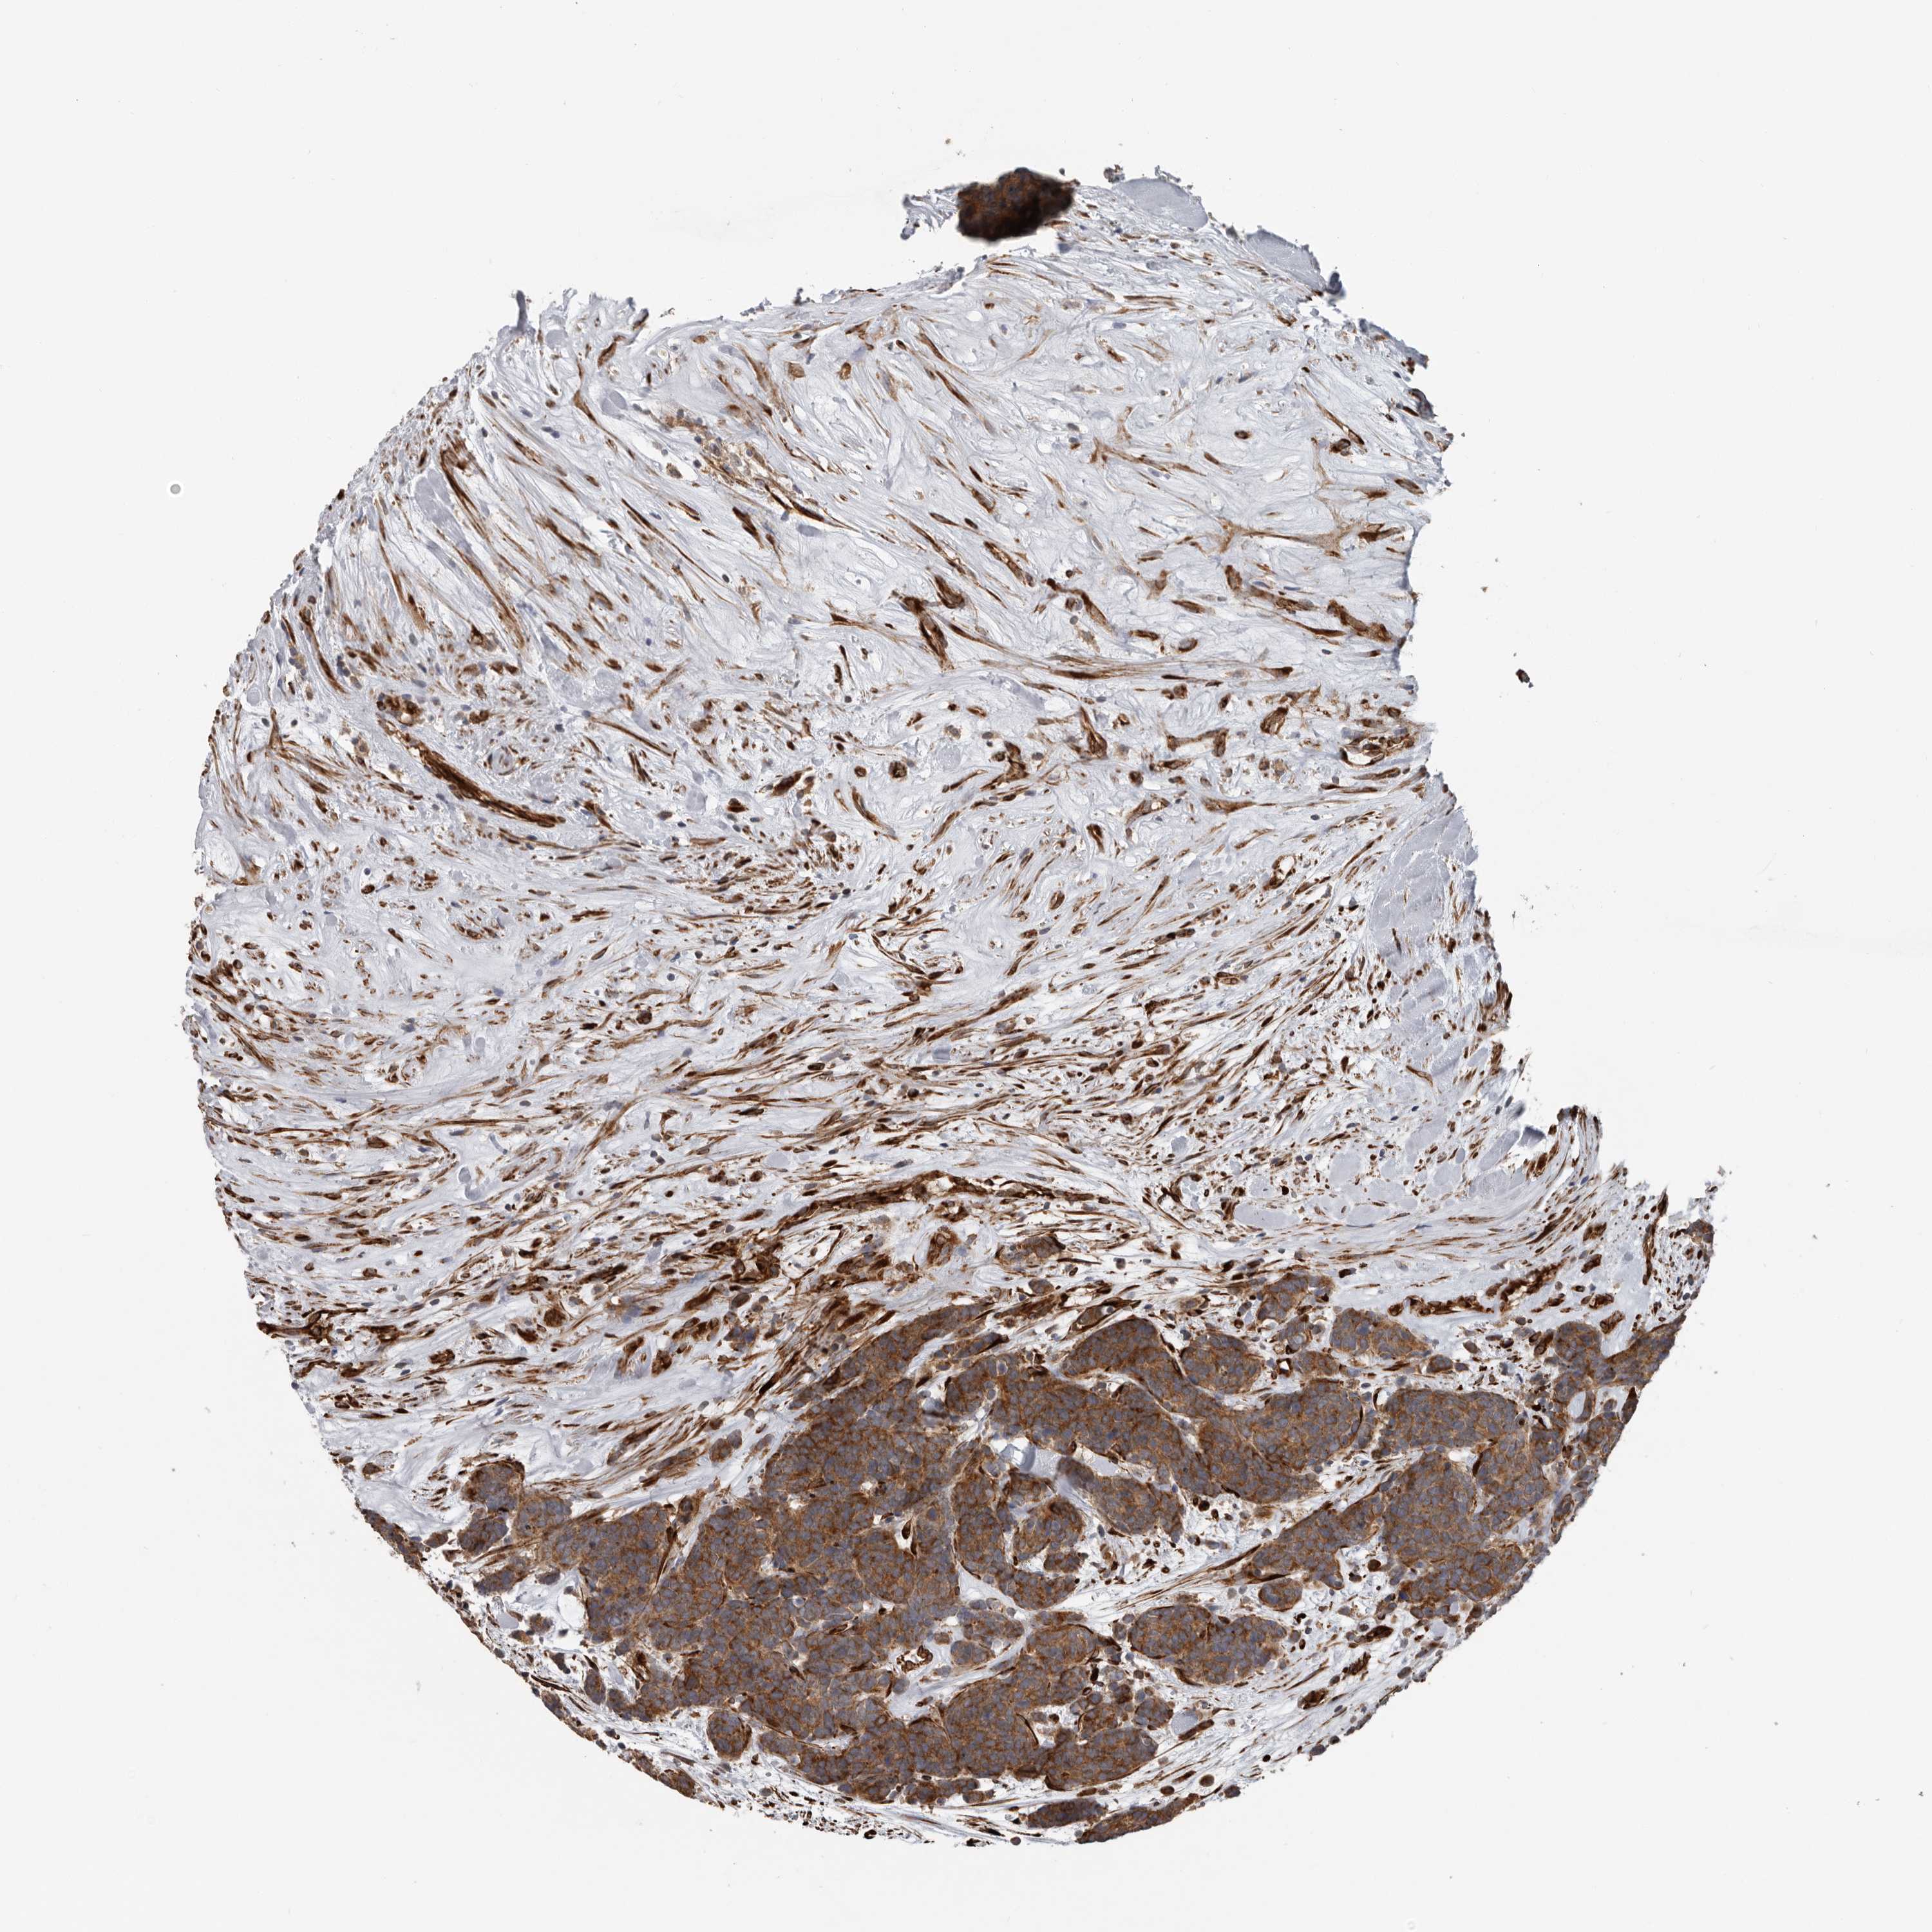

CARCINOID - Protein expressioni

A mouse-over function shows sample information and annotation data. Click on an image to view it in a full screen mode. Samples can be filtered based on level of antibody staining by selecting one or several of the following categories: high, medium, low and not detected. The assay and annotation is described here.

Antibody stainingi

Antibody staining in the annotated cell types in the current human tissue is reported as not detected, low, medium, or high, based on conventional immunohistochemistry profiling in selected tissues. This score is based on the combination of the staining intensity and fraction of stained cells.

Each image is clickable and will lead to virtual microscopy that enables deeper exploration of all samples and also displays staining intensity scores, fraction scores and subcellular localization as well as patient and tissue information for each sample.

Antibody HPA028355

Antibody HPA028357

Staining

High

Medium

Low

Not detected

Intensity

Strong

Moderate

Weak

Negative

Quantity

>75%

75%-25%

<25%

None

Location

Nuclear

Cytoplasmic/membranous

Cytoplasmic/membranous,nuclear

Carcinoid, malignant, NOS

Carcinoma, NOS